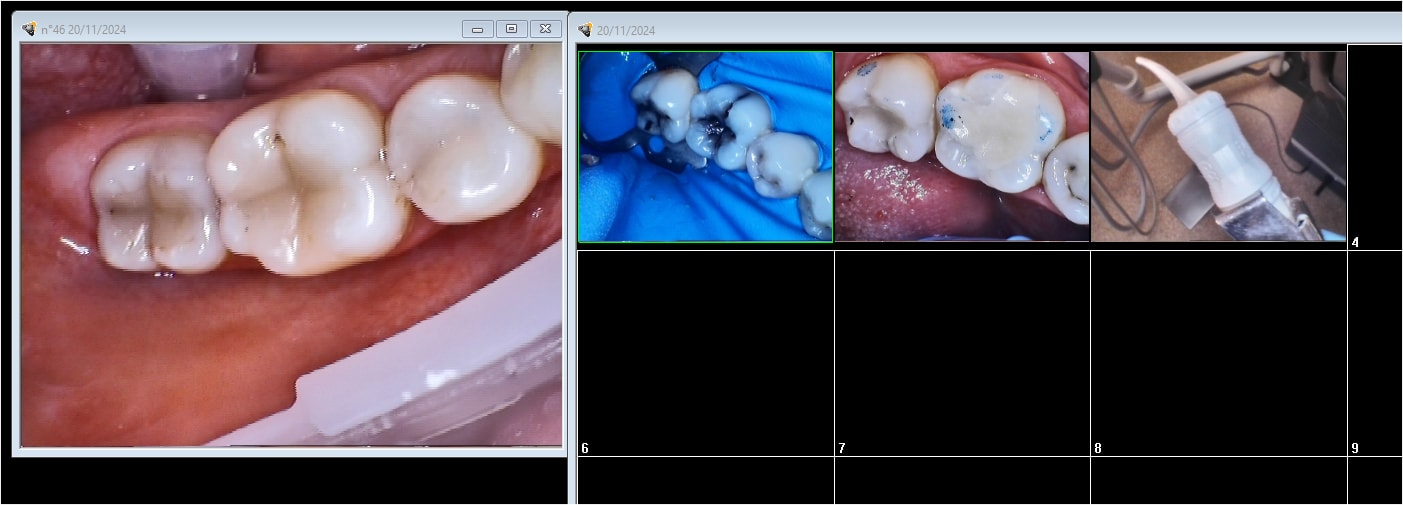

j'ai posé 2 CVI sur 36 37 c'est rapide et reposant . Ca tient la route comparé aux compos secteur 4 . Je vois pas pourquoi on se fait chier la patiente a fait une crise d'angoisse avec la digue du coup j'ai été au plus rapide.

fuji II LC